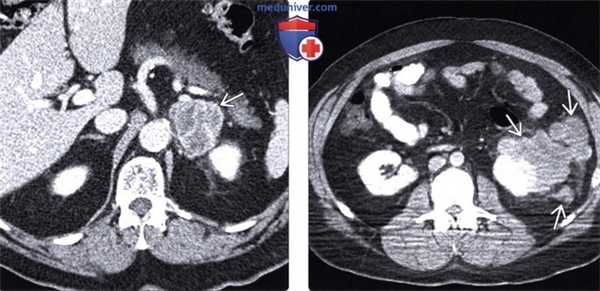

(Слева) При аксиальной КТ с контрастным усилением определяется объемное образование, интенсивно накапливающее контраст, неоднородной, дольчатой структуры в левом надпочечнике у пациента с меланомой, пролеченного десять лет назад. Путем биопсии было установлено, что данное образование является метастатической меланомой.

(Справа) При аксиальной КТ с контрастом выявлено несколько отдельно лежащих объемных образований неоднородной, дольчатой структуры, расположенных в околопочечных тканях у пациента с меланомой. Метастазы меланомы имеют уникальную предрасположенность к поражению околопочечных тканей.

• Почки:

о Уникальная предрасположенность к околопочечным тканям:

- Большое изолированное объемное образование в околопочечном пространстве должно наводить на мысль о меланоме

- Могут поражаться почки, мочевой пузырь или собирающая система (почек)

о Единичное или множественные поражения различного размера, которые могут выглядеть солидными либо «кистозными» (но никогда не выглядят как простая киста)

• Надпочечники:

о Вторичные поражения надпочечников при меланоме неотличимы от метастазов других опухолей на изображениях:

- Обычно гиподенсные, дольчатые, неоднородные по структуре

о Может возникать надпочечниковая недостаточность (болезнь Адиссона) в результате деструкции железы

(Слева) На КТ с контрастным усилением в корональной плоскости определяется усиливающееся при контрастировании объемное образование в мочевом пузыре. Обратите внимание также на гиперденсную зону в уретре, накопившую контраст. Все эти изменения являются проявлениями метастатической меланомы. Поражение мочевого пузыря неотличимо от первичной опухоли без анамнеза заболевания.

(Справа) При аксиальной КТ с контрастным усилением выявлено накапливающее контраст объемное образование в желчном пузыре. В анамнезе - меланома, и это поражение медленно увеличивается в размерах с течением времени. Меланома - самая частая причина метастазов в желчном пузыре.